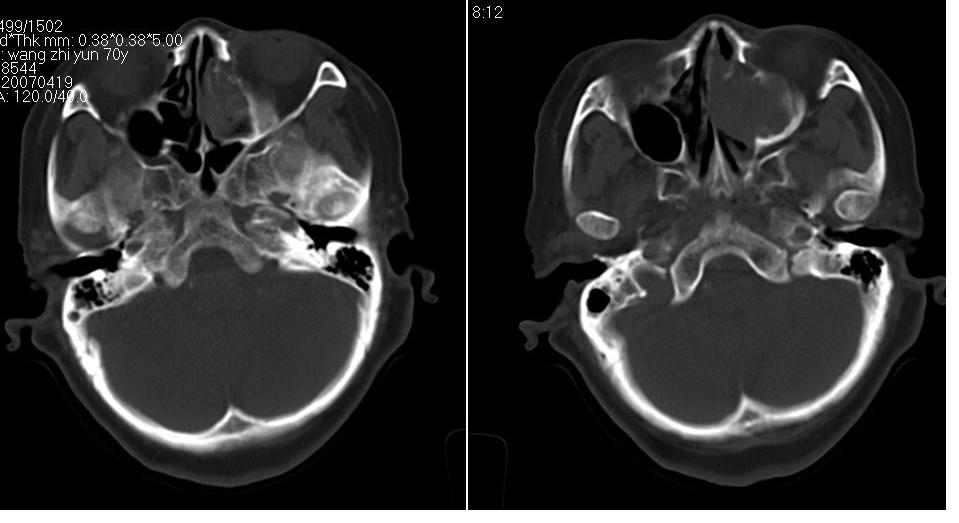

女 70岁,左侧上颌窦腔内肿物。

左侧颌窦内可见高密度影充填,窦壁增厚 考虑 左颌窦囊肿 慢性炎症

左侧上颌窦内软组织影,略呈膨胀性,窦壁骨质增生硬化,考虑为黏膜下囊肿.左侧筛窦炎

窦壁骨质增厚,密度增高,窦口扩大,考虑慢性炎症,息肉样变。

左侧上颌窦内软组织密度影,窦壁骨质增厚,密度增高,窦口扩大,考虑左侧上颌窦慢性炎症,息肉样变。

左侧上颌窦窦内可见高密度影充填,窦壁增厚,考虑左上颌窦窦囊肿,慢性炎症.